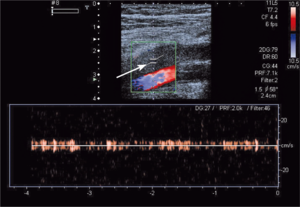

Najczęstszą kliniczną manifestacją zespołu antyfosfolipidowego jest zakrzepica żylna, zwłaszcza żył głębokich kończyn dolnych (ryc. 1). Zakrzepica tętnicza występuje rzadziej i dotyczy głównie tętnic mózgowych (ryc. 2), ale może także dotyczyć tętnic wieńcowych lub innych obszarów naczyń obwodowych [7].